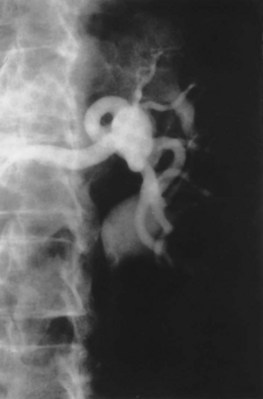

Medial fibroplasia accounts for 75% to 80% of fibrous lesions primarily in women between 25 and 50 years of age. With angiography, arteries demonstrate a “string of beads” in the distal two thirds of the main renal artery and its branches (Fig. 54–43). Multiple microaneurysms can also be appreciated. An estimated 33% demonstrate progression, whereas complete occlusion is rare.

Figure 54–43 Selective right renal angiogram demonstrating medial fibroplasia “beads on a string” in a solitary right kidney.

Perimedial (subadventitial) fibroplasia accounts for 10% to 15% of fibrous lesions and is limited to the renal arteries. Angiographically the appearance is similar to that of medial fibroplasia but there are no microaneurysms and extensive collateral circulation is present (Fig. 54–44). Without intervention this entity leads to severe stenosis and progressive obstruction with ischemic nephropathy. The disease often afflicts young females.

Figure 54–44 Selective right renal angiogram demonstrating perimedial (subadventitial) fibroplasia with decent collateral vasculature.